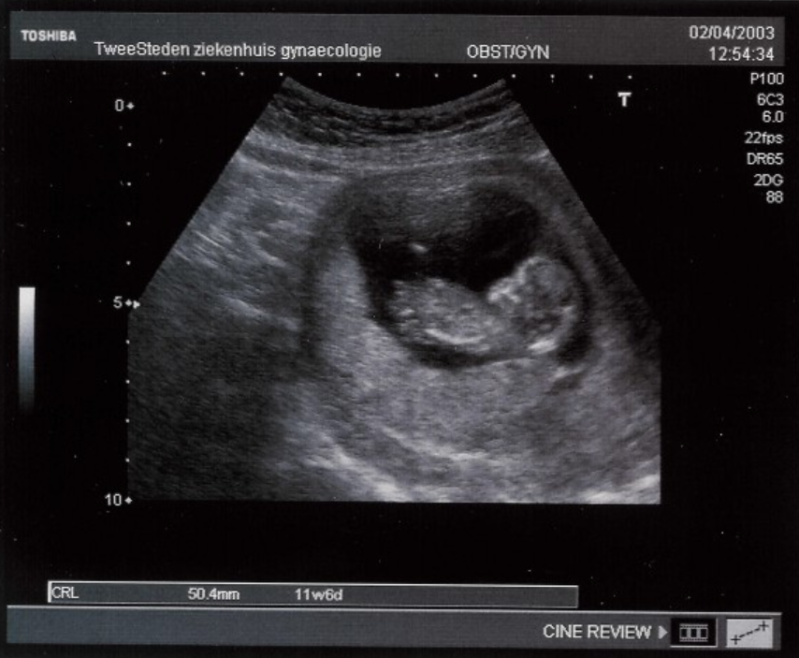

Echografie

De laatste techniek is echografie. Hierbij gebruikt men ultrasound. Zoals de naam al doet vermoeden gebruikt deze techniek geen enkele elektromagnetische straling en is dus niet schadelijk voor de mens. Wat men opneemt is de echo van het geluid als het geluid reflecteert op een densiteitsverandering. Zo goed als iedereen heeft al een echografie ondergaan, namelijk nog voor dat we zijn geboren.